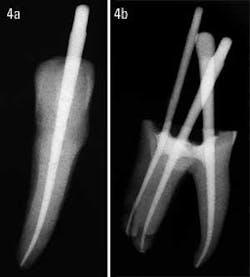

Glass ionomer cements in the past had some handling inconsistencies. Generally, the working time was not sufficient, the mix could not be altered, and the radiopacity was moderate, at best. Activ GP sealer has been modified in such a manner that, when mixed on a chilled glass slab, it will easily give a 20-minute working time. If the working time needs to be extended, simply add more liquid and mix it like zinc phosphate cement. The extra liquid is not a concern because the use of glass ionomer in a root canal is not about excessive bond strength, but rather about sealability. The radiopacity of Activ GP sealer has also been increased significantly, with the result being that the cases will not only work well, they will also look good (figures 4a and 4b).